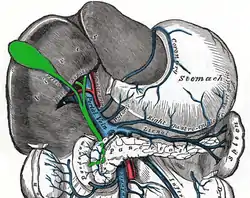

The cystic artery (also known as bachelor artery) is (usually) a branch of the right hepatic artery that provides arterial supply to the gallbladder and contributes arterial supply to the extrahepatic bile ducts.

The cystic artery arises from the right hepatic artery in about 80% of cases.[1]

It usually passes posterior to the common hepatic duct within the cystohepatic triangle. Within the triangle, it is usually superior to the cystic duct (if it does not pass superior to the cystic duct, it may be situated outside the triangle).[1]

Upon reaching the superior aspect of the neck of the gallbladder, it splits into superficial and deep branches. These branches then form an anastomotic network over the surface of the body and fundus of the gallbladder.[1]

The cystic artery additionally emits fine branches that contribute to the arterial supply of the extrahepatic bile ducts.[1]

It must be identified and ligated in operations that remove the gallbladder (cholecystectomies).